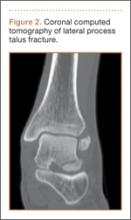

An increasingly common injury among snowboarders is a fracture of the lateral process of the talus; this injury accounts for 32% of snowboarders’ ankle fractures.6 The lateral process of the talus—wedge-shaped and covered in articular cartilage—is involved in the subtalar and ankle joints.9 A fracture here is often misdiagnosed as an ankle sprain (Figures 1–3).6,9,10 The exact mechanism of injury remains controversial, and several biomechanical factors seem to be involved. Funk and colleagues11 conducted a cadaveric study and concluded that eversion of an axially loaded, dorsiflexed ankle may be the primary injury mechanism for fracture. Furthermore, snowboarders have their feet in a position perpendicular to the board, and a fall parallel to the board could increase the eversion force on the ankle of the leading leg. Valderrabano and colleagues9 conducted a clinical study of 26 patients who sustained this injury from snowboarding. All the patients reported they had felt an axial impact from falling, jumping, or unexpectedly hitting a ground object, and 80% reported a rotational movement in the lower leg during the impact. The authors concluded that axial loading and dorsiflexion were not the only factors involved in lateral process talus fractures, and an external moment is necessary to cause this injury from a forward fall.9